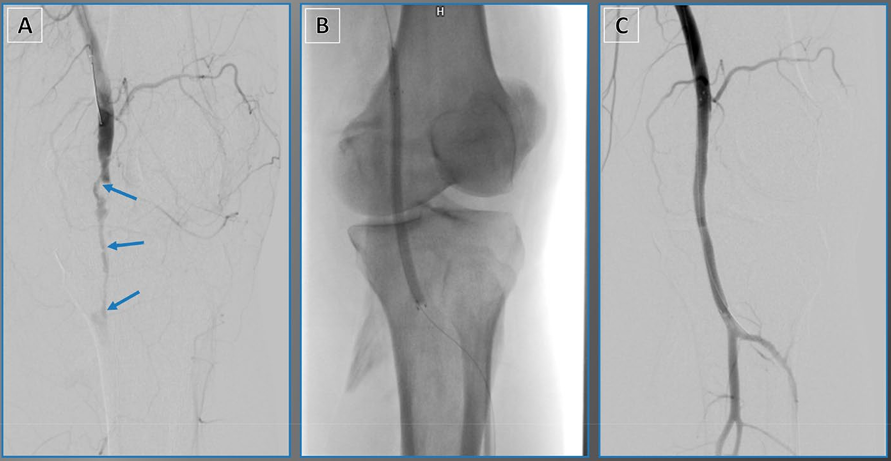

原文图1. 使用外部器械进行病变修饰。(A)压裂技术:利用液压裂解深层钙化斑块。(B)DECIAP技术:使用动脉钳夹碎钙化斑块。DECIAP:钳夹诱导动脉斑块开裂直接内膜切除术。

压裂治疗前后及球囊血管成形术后病变形态与IVUS评估的MLA代表性病例。A 初始血管造影显示右侧股总动脉存在重度钙化斑块。B 初始IVUS评估示术前最小管腔面积(MLA)为2.1 mm²(管腔直径:1.7 × 1.3 mm)。C、D 使用7.0 mm非顺应性球囊行球囊血管成形术后,后续血管造影及IVUS显示残余狭窄33%,术中MLA为5.8 mm²(管腔直径:3.0 × 1.7 mm)。E 压裂治疗后,最终血管造影显示满意影像,狭窄率17%。F 压裂后IVUS评估显示术后MLA为20.5 mm²(管腔直径:6.1 × 4.3 mm)。缩略语:IVUS,血管内超声;LD,管腔直径;MLA,最小管腔面积。